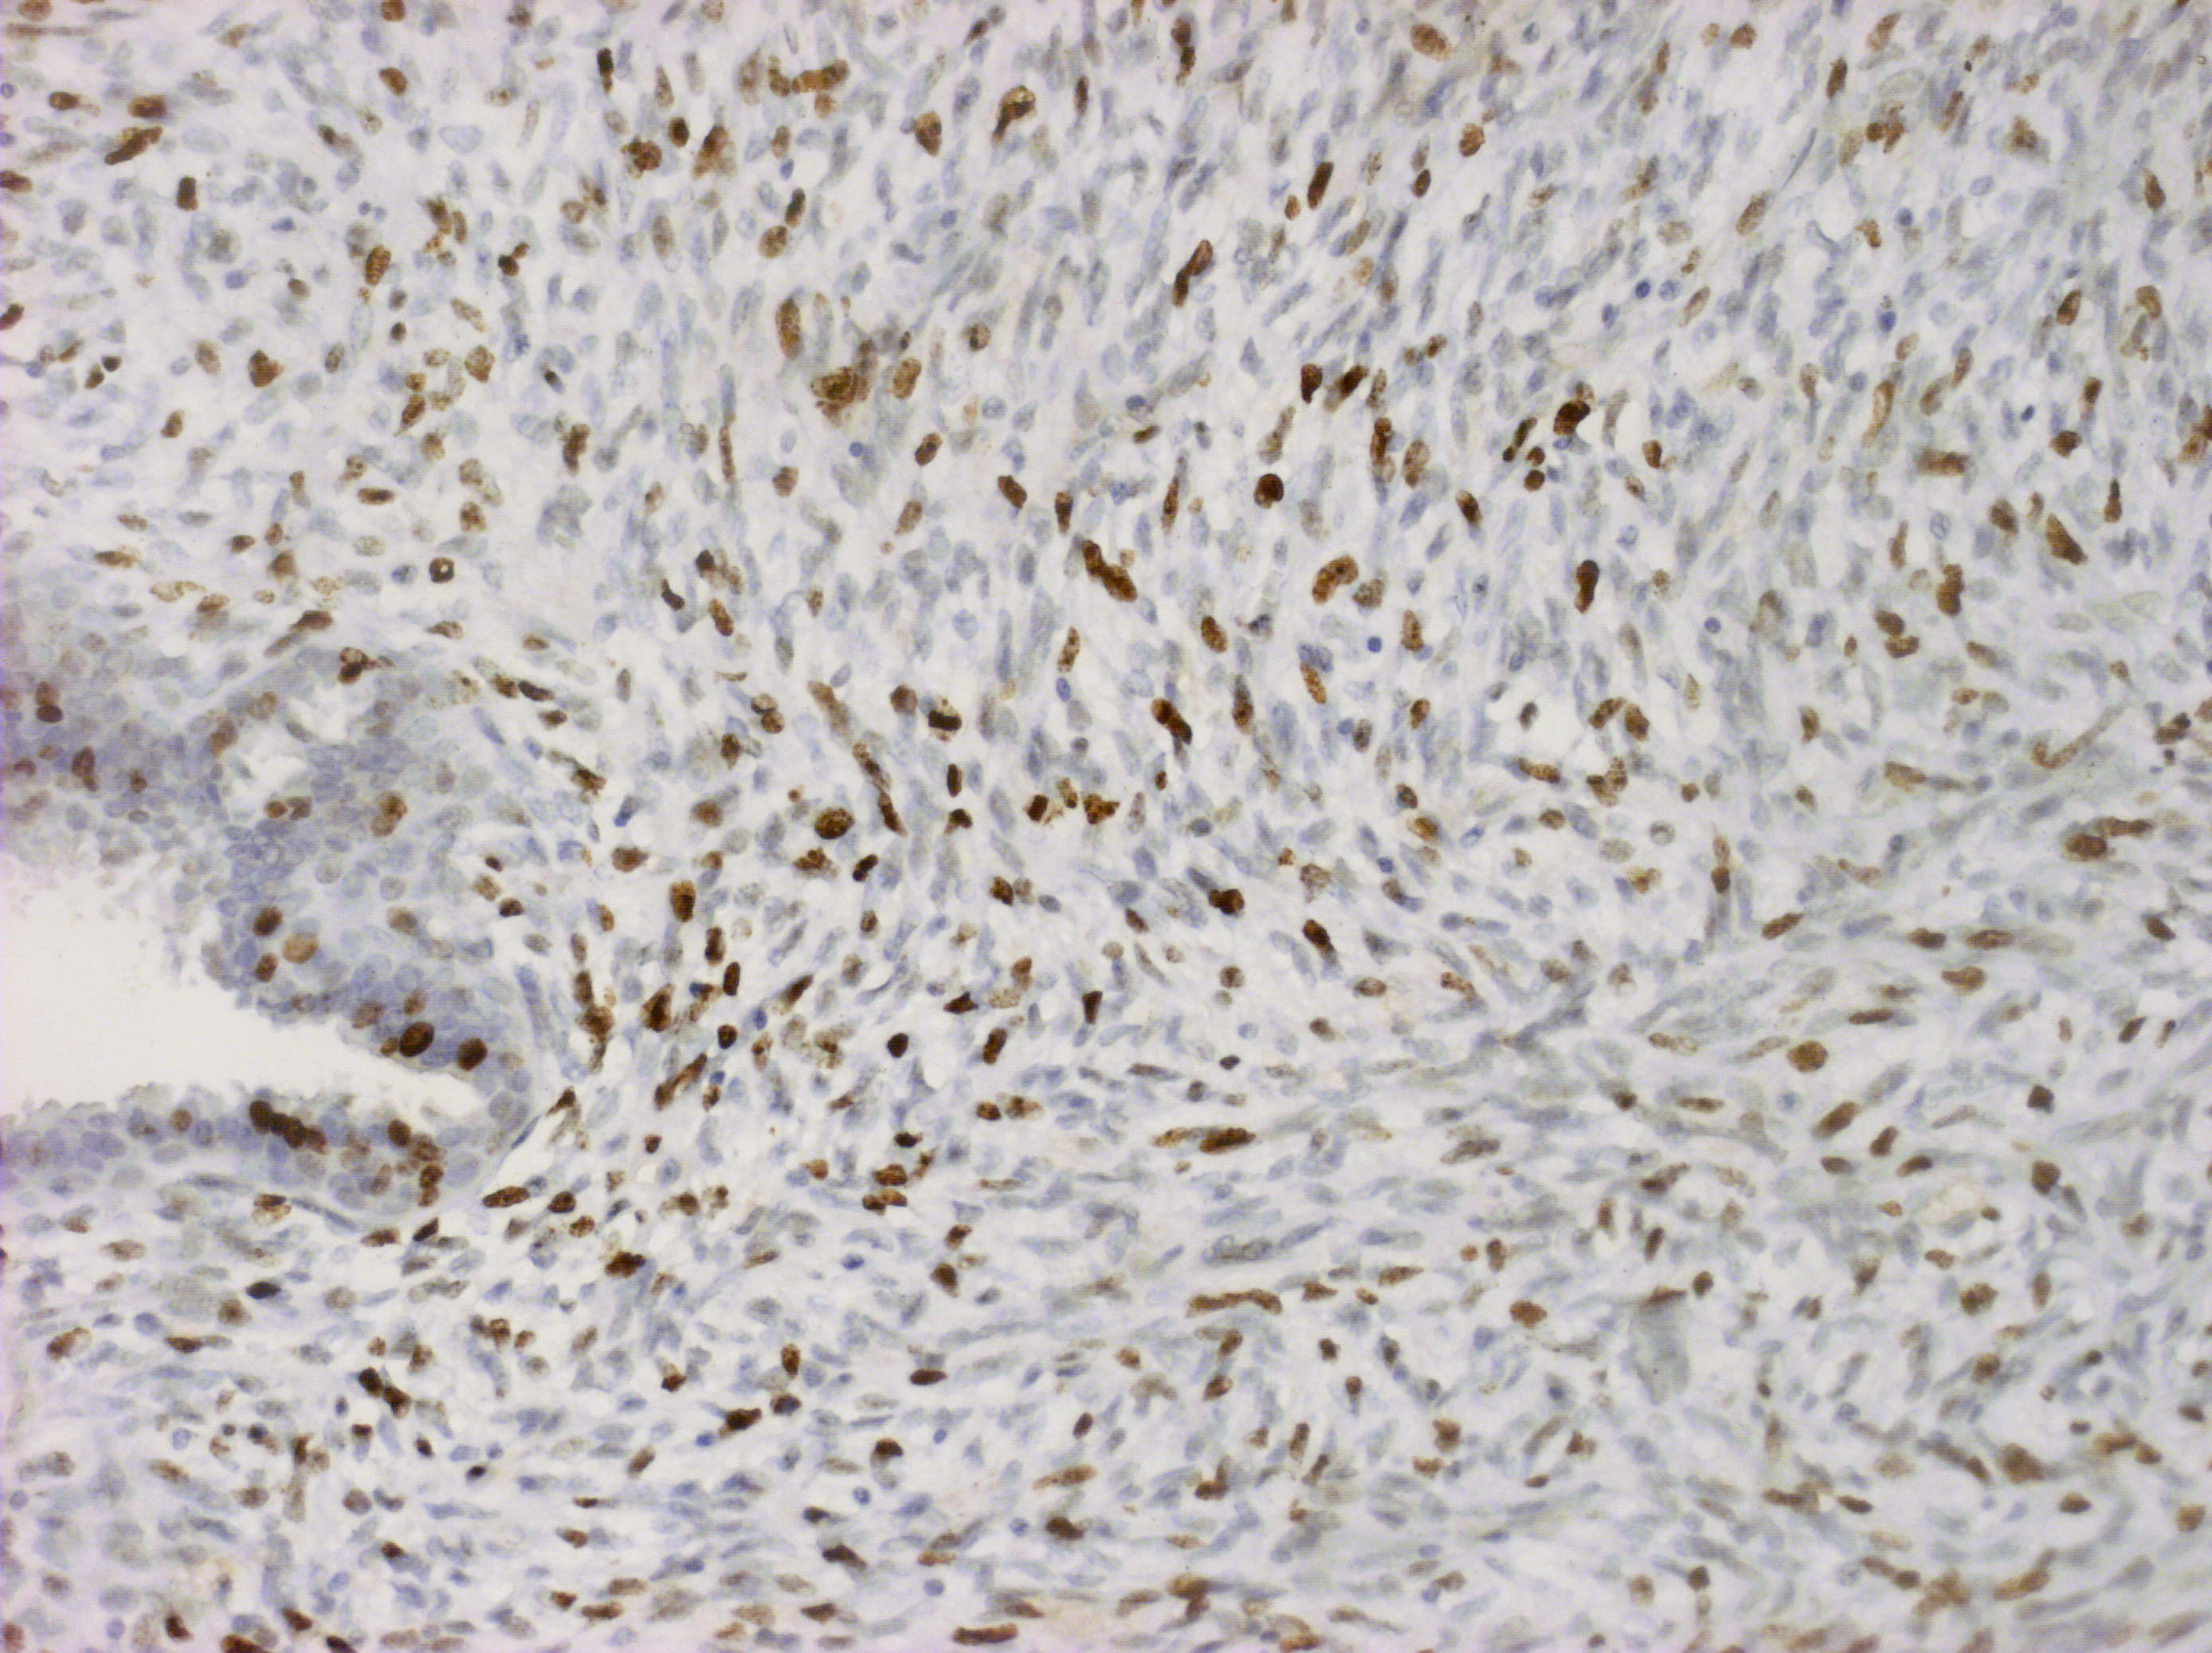

Матеріали та методи. Для ІГХ-дослідження було відібрано 60 парафінових блоків пухлин, у яких гістологічно було верифіковано діагноз саркоми (42) та філоїдної пухлини (18). ІГХ-дослідження проводили з використанням спектра відповідних антитіл, який включав маркери панцитокератинів (клон AE1/AE3); ERG (клон EP111); SOX-10 (клон EP268); TLE1 (клон 1F5); кальдесмону (клон h-CD); міогеніну (Myf-4) (клон F5D); MyoD1 (клон EP212); десміну (клон D33); MDM2 (клон 1B10); CDK4 (клон EP180); CD68 (клон PG-M1); CD34 (клон QBEnd 10); CD31 (клон JC70A); бета-катеніну (клон betaCatenin-1); гладеньком’язового актину альфа (клон 1A4); актину (клон HHF35); епітеліального мембранного антигену (EMA, MUC1) (клон E29). Також визначали рівень експресії маркера проліферації Ki-67 (клон MIB-1). Дослідження проводили в лабораторії CSD Health Care, м. Київ.

Результати дослідження та їх обговорення. Після проведених імуногістохімічних досліджень виявилось, що із 12 сарком без уточненого гістотипу в 9 випадках були плеоморфні саркоми, у 2-х – міофібробластні саркоми, та одна остеосаркома. Із 27 блоків ангіосарком імуногістохімічно було підтверджено 17 (63,0 %), інші 10 (37,0 %) виявились карциномами. Фібросаркоми (три гістологічні блоки) були повністю підтверджені імуногістохімічно. Серед 18 гістологічних блоків філоїдних пухлин проміжного типу у двох випадках (11,1 %) було встановлено злоякісний варіант ФП.